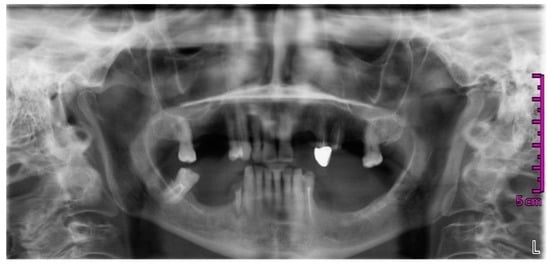

2. Case Report